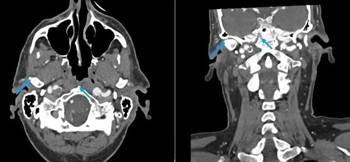

This patient’s CT angiography also returned the surprising finding of bilateral chronic carotid artery dissections in the high internal carotid arteries. This is another turbulence-creating vascular disorder that predisposes to thromboembolism. He had a memory of a terrible headache that put him in bed for three days when he was in his 20s, 40 years earlier; maybe that was when the dissections happened? The carotid arteries were also noted to be chronically enlarged, which probably explains the anisocoria.

Arrows point to patient's cartoid dissections